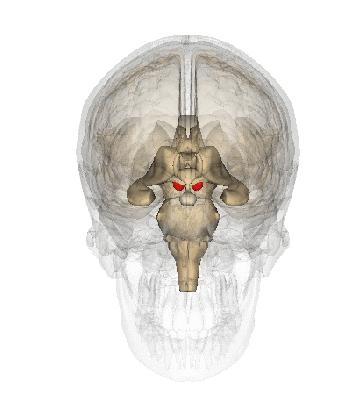

14. 急性颅内高压所致脑疝的分型

点击图片可查看大图详情